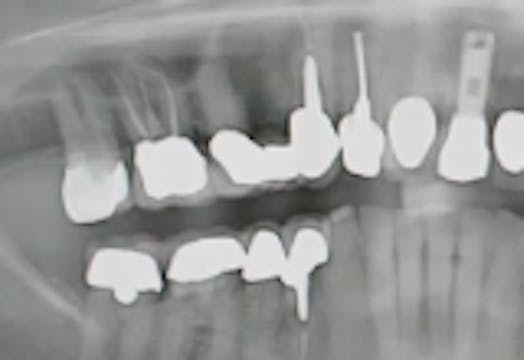

CLINICAL VIDEO All-on-4 Upper Jaw Implant Surgery - Patient consultation, oral e

IMPLANT DENTISTRY • 17m